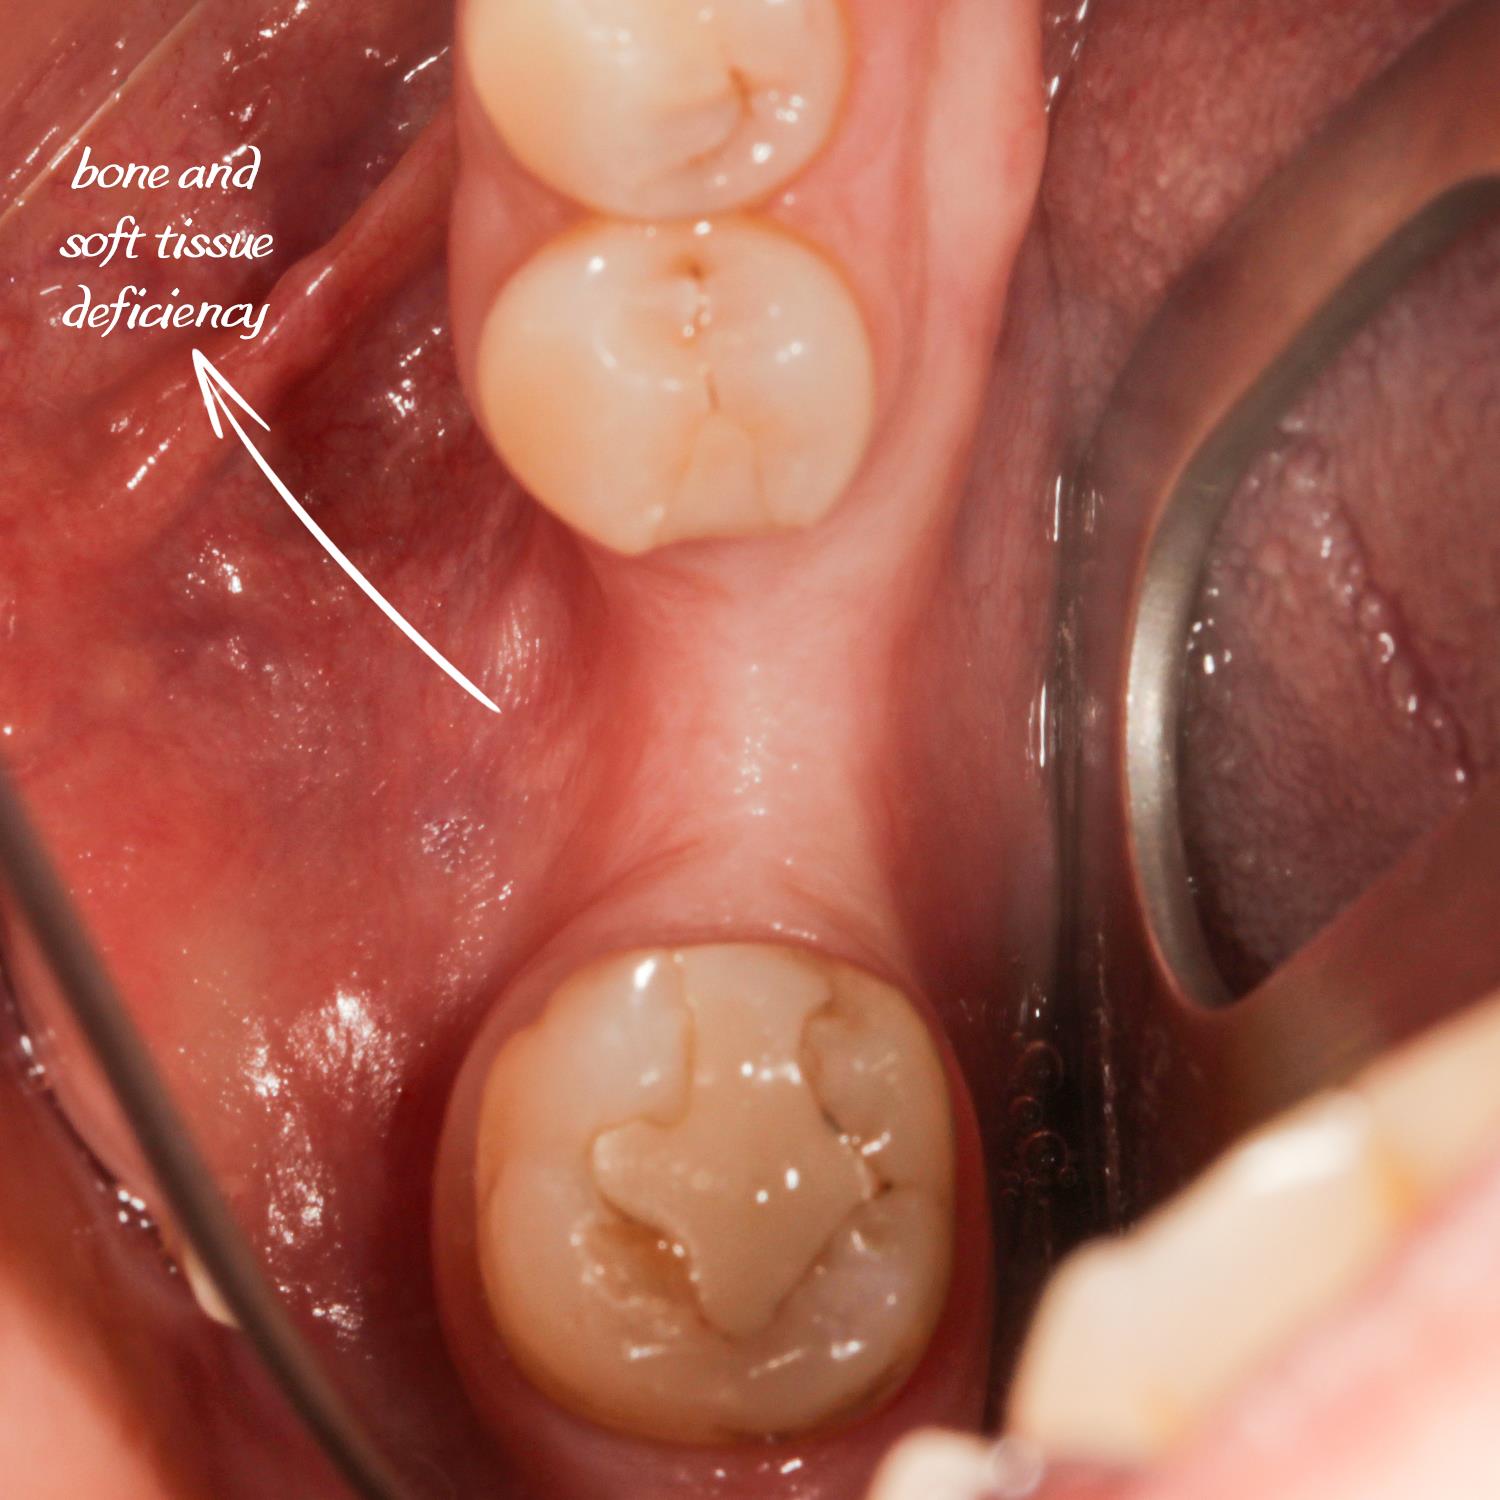

Kemik tozu ve PRF ile sert ve yumuşak doku ogmentasyonu yapıldı.